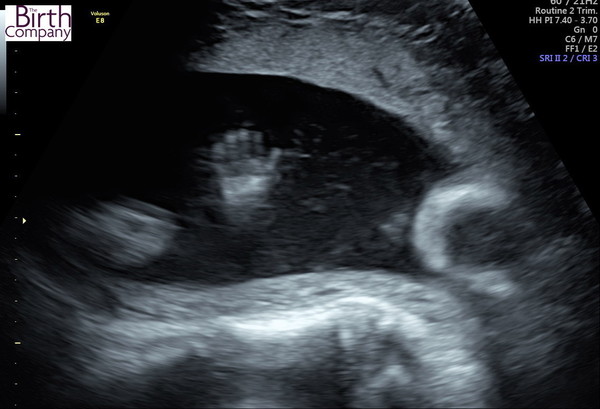

Emmasmum2013 · 06/04/2018 12:23

Here she is, sucking her fingers.

Awww! That's lovely :)

Lovely scan pics!

Aww congrats @Emmasmum! Beautiful girl!

Cute photo, Emmasmum. Glad your scan went well.

Thanks everyone! It was an amazing scan.

I was also told I have an anterior placenta so that explains why I mainly feel movement really low down and at the sides.